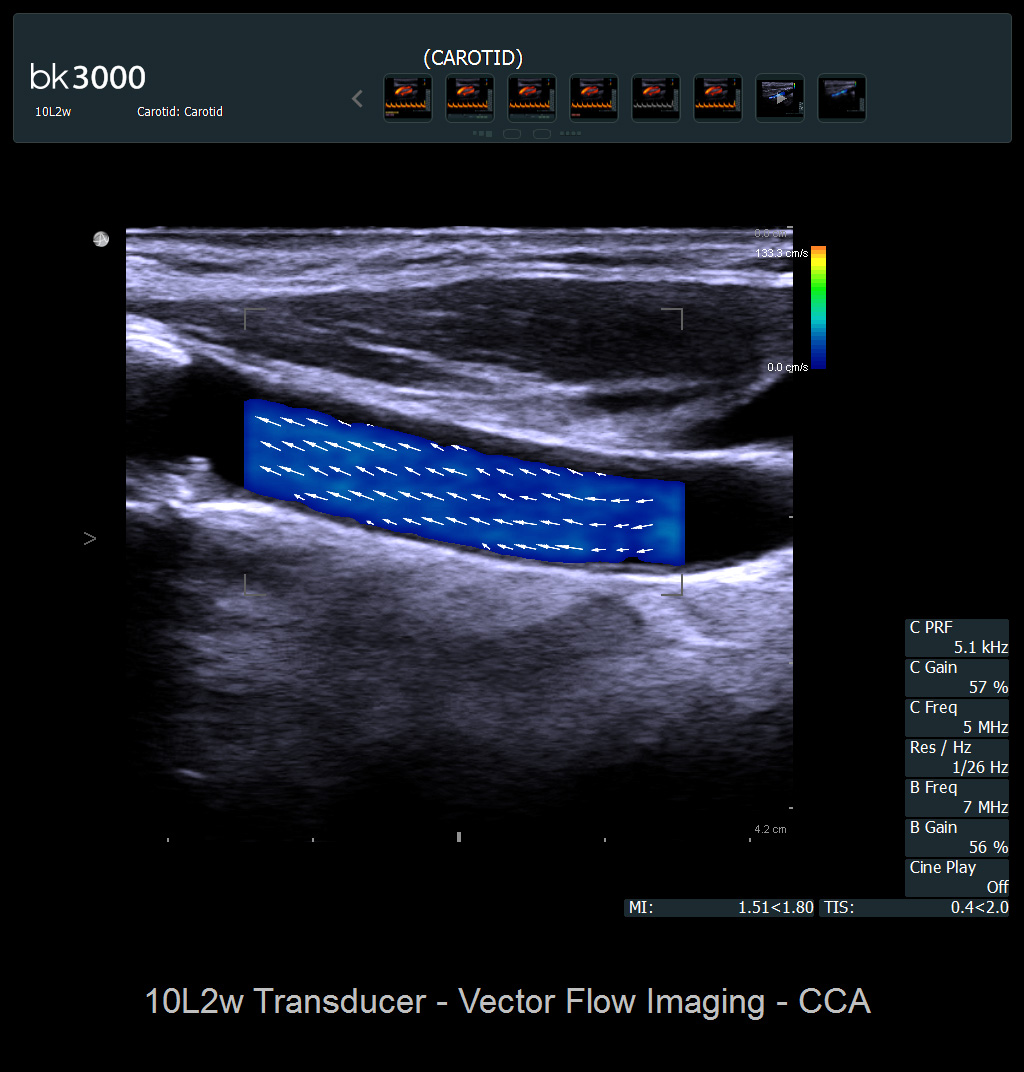

Der bk3000 liefert ein neues Maß an Geschwindigkeit und Leistung

Ultraschallbilder unterstützen Ihre wichtigen Entscheidungen. Das heißt, je klarer die Darstellung ist, desto sicherer können Sie bei Ihren Behandlungsentscheidungen sein. Aus diesem Grund liefert der bk3000 hervorragende Bilder mit hoher räumlicher, zeitlicher und kontrastreicher Auflösung, mit denen Sie Läsionen schnell erkennen und gezielte Biopsien durchführen können.

Die Detailerkennbarkeit und die Geschwindigkeit sind im Arbeitsalltag wichtig - der bk3000 bietet Abhilfe und liefert schnell hochauflösende Bilder. Die automatische Bildverstärkung (No Touch Auto Gain) optimiert das Bild sofort und passt es Ihren Anforderungen an. Ergänzende Modi, einschließlich Elastographie und Kontrastbildgebung, helfen Ihnen, schnell und sicher verdächtige Bereiche zu identifizieren und die Notwendigkeit zu reduzieren, Ihre Patienten:innen an andere Abteilungen zu überweisen.